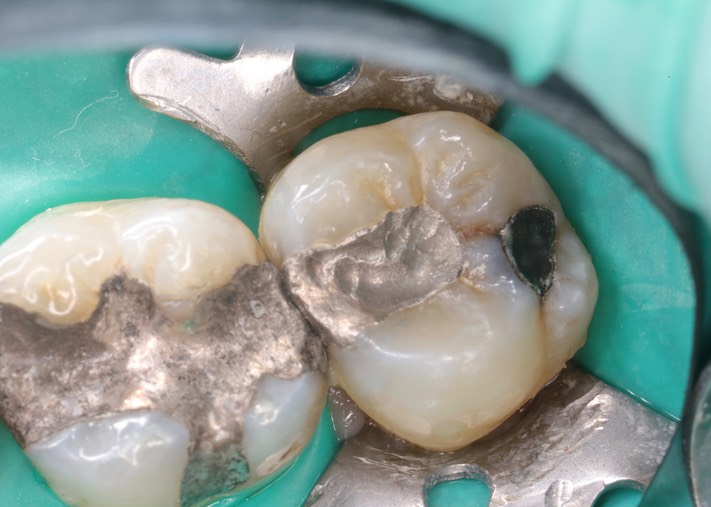

Dr. May Chang’s cases

March 1, 2012